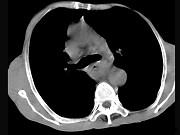

问题 女,71岁,进食时有梗阻感,进行性加重半年,影像检查如图,最可能的诊断是()

选项 A.贲门失弛缓症 B.食道癌并纵隔淋巴结转移 C.食道良性狭窄 D.返流性食道炎 E.食道静脉曲张

答案 B